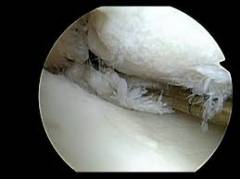

- Суставные мениски (правый и левый). Мыщелки бедра больше, чем мыщелки большеберцовой кости. Это несоответствие компенсируется хрящами – наружным и внутренним менисками. Верхняя часть мениска соответствует форме мыщелка бедренной кости, а нижняя – мыщелку большеберцовой кости. Мениски также выполняют амортизирующую функцию. Артроскопию часто проводят при подозрении на их повреждение.

| Повреждения суставных хрящей | Артроскопия позволяет выявлять повреждения, которые не обнаруживаются при других исследованиях. Врач может удалить патологические разрастания и осуществить пластику дефектов. |

| Повреждения и заболевания суставных хрящей | Артроскопия позволяет обнаружить повреждения суставных хрящей, которые могут быть не видны при других исследованиях. В процессе вмешательства врач может удалить патологические разрастания на хряще и выполнить пластику дефектов. |